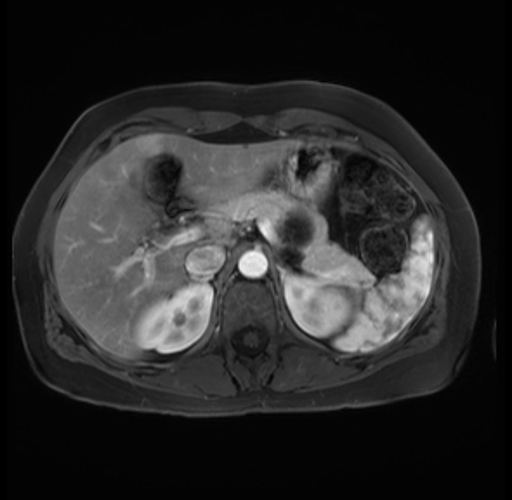

Imaging Analysis

Look through the patient's CT scan to identify any areas of concern for the necessary procedure.

Based on your CT findings, which issue(s) are present and would give reason for "planned slowing down moment(s)" in this case?

Considering a standard distal pancreatectomy procedure, what step(s) of the operation would you do differently in this case?